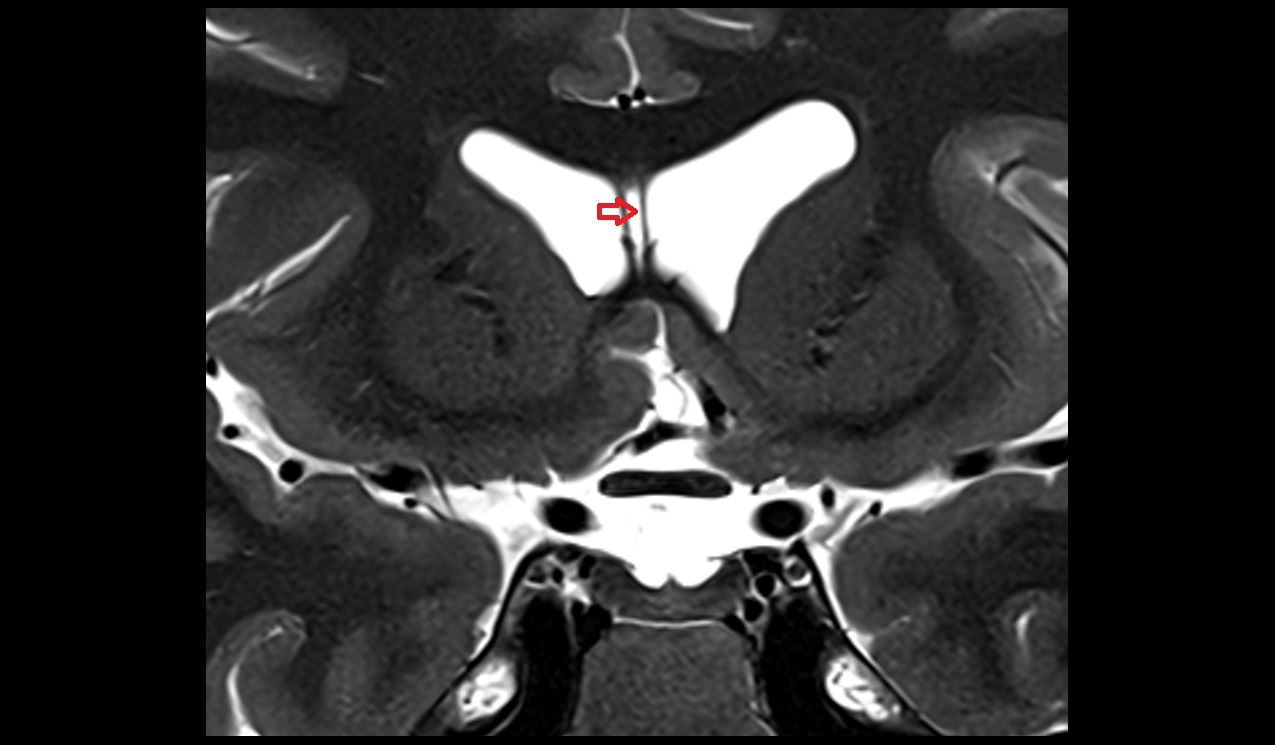

- Interventricular foramen